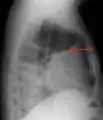

A large left-sided pleural effusion as seen on an upright chest X-ray

Imaging

A pleural effusion appears as an area of whiteness on a standard posteroanterior chest X-ray.[12] Normally, the space between the visceral pleura and the parietal pleura cannot be seen. A pleural effusion infiltrates the space between these layers. Because the pleural effusion has a density similar to water, it can be seen on radiographs. Since the effusion has greater density than the rest of the lung, it gravitates towards the lower portions of the pleural cavity. The pleural effusion behaves according to basic fluid dynamics, conforming to the shape of pleural space, which is determined by the lung and chest wall. If the pleural space contains both air and fluid, then an air-fluid level that is horizontal will be present, instead of conforming to the lung space.[13] Chest radiographs in the lateral decubitus position (with the patient lying on the side of the pleural effusion) are more sensitive and can detect as little as 50 mL of fluid. Between 250 to 600mL of fluid must be present before upright chest X-rays can detect a pleural effusion (e.g., blunted costophrenic angles).[14]

Chest computed tomography is more accurate for diagnosis and may be obtained to better characterize the presence, size, and characteristics of a pleural effusion. Lung ultrasound, nearly as accurate as CT and more accurate than chest X-ray, is increasingly being used at the point of care to diagnose pleural effusions, with the advantage that it is a safe, dynamic, and repeatable imaging modality.[15] To increase diagnostic accuracy of detection of pleural effusion sonographically, markers such as boomerang and VIP signs can be utilized.[16]